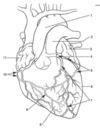

Which number(s) below are part of the interventricular septum?

A

3&8